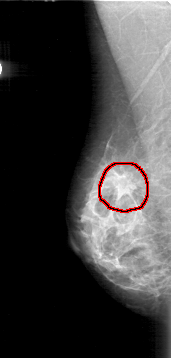

FILE: D_4185_1.RIGHT_MLO.OVERLAY

TOTAL_ABNORMALITIES 1

ABNORMALITY 1

LESION_TYPE MASS SHAPE IRREGULAR MARGINS SPICULATED

ASSESSMENT 5

SUBTLETY 4

PATHOLOGY MALIGNANT

TOTAL_OUTLINES 1

BOUNDARY

RIGHT_MLO LINES 5011 PIXELS_PER_LINE 2386 BITS_PER_PIXEL 12 RESOLUTION 43.5 OVERLAY